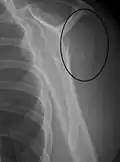

A fracture of the greater tuberosity as seen on AP X ray -

A fracture of the greater tuberosity of the humerus -

Fracture of the greater tuberosity of the humerus -